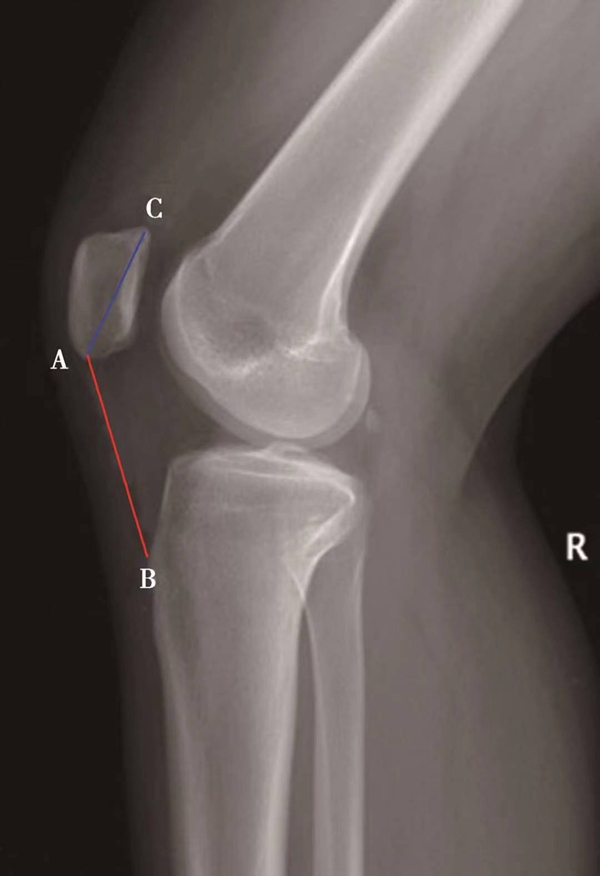

测量胫骨后倾角时先要观察胫骨上段及其与腓骨的位置关系,选择无明显胫骨旋转的,胫骨平台轮廓清晰的膝关节X侧位片。方法1测得的胫骨后倾角范围是11.74°±3.87°,方法2测得的胫骨后倾角范围是8.91°±3.57°,方法3测得的胫骨后倾角范围是6.21°±3.51°。

图15 胫骨后倾角的评估

用量角器测量胫骨内侧平台前后缘连线分别与胫骨中上段前侧骨皮质切线的垂线(图15A)、胫骨结节下胫骨中上段轴线的垂线(图15B)以及胫骨后侧皮质切线的垂线(图15C)的夹角,即胫骨后倾角(∠AOB)